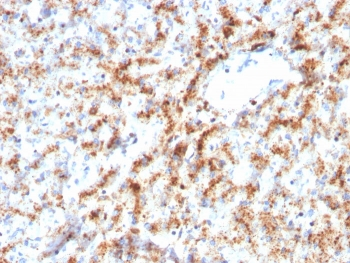

Cathepsin D Antibody

| Description | Cathepsin D Antibody |

| Tested applications | FC, ICC, IHC, IP, WB |

| Reactivity | Human, Mouse |